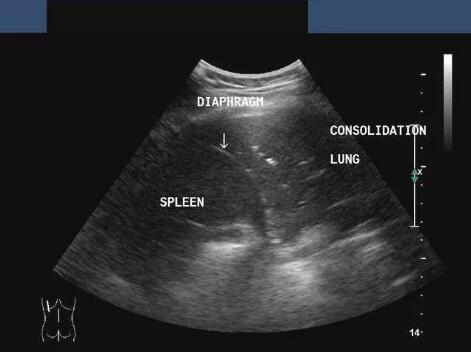

No.3 超声

无电离辐射,适用于实性器官,如肝胆脾胰,子宫及附件,肾输尿管等的检查,因为气体会影响超声的穿透,因此对肺脏这种含气器官原发灶的诊断不敏感,在肺癌患者中主要用来评价腹部脏器、淋巴结等是否发生转移,也用来进行胸水定量及定位。